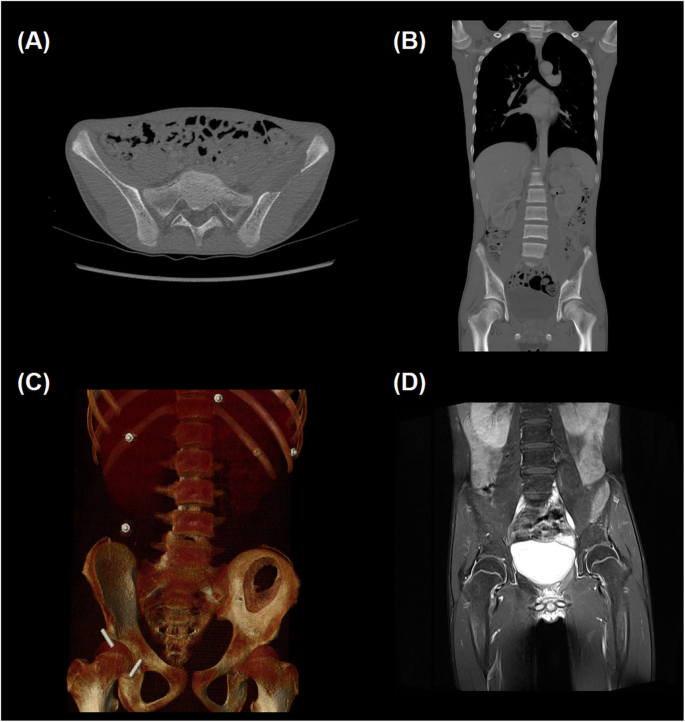

Given the palpable mass and reported symptoms of emesis and constipation, a plain film abdominal radiograph was performed on admission to evaluate the abdominal mass and assess for possible obstruction. This identified large fecal loading of the colon and a lytic lesion within the left iliac wing (Fig. 1). Subsequent computed tomography (CT) and magnetic resonance imaging (MRI) imaging showed the lesion arising within the bone, measuring 13 × 5.1 × 5.8 cm and a scalloped appearance with a T2 intense soft tissue component slightly projecting beyond the anterior table of the iliac bone (Fig. 2). Thyroid ultrasound and Nuclear Medicine technetium 99 m Sestamibi scan were consistent with the identification of a solitary left superior parathyroid adenoma (Fig. 3).